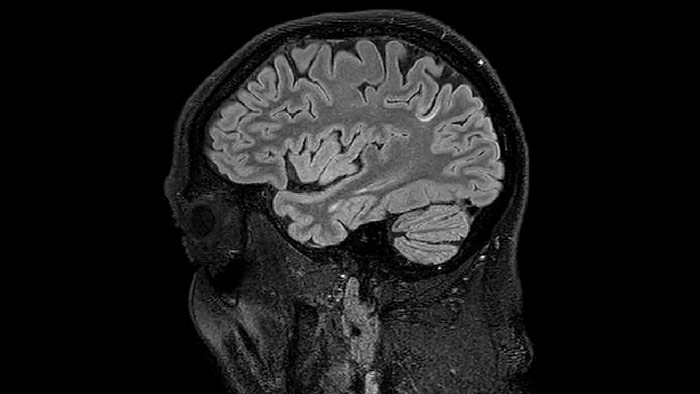

Sagittal 3D FLAIR with 0.3 mm3 voxel volume acquired in 5:12 min. using Compressed SENSE showing a (juxta)cortical MS lesion.

T1 - weighted

Myelin water imaging (echo 1)

T1 - Weighted, Myelin Water Fraction Superimposed

Spinal cord coverage

Smaller, more isotropic voxels

Excellent detail in quantitative maps

Images courtesy of Adam Dvorak, Department of Physics and Astronomy, University of British Columbia